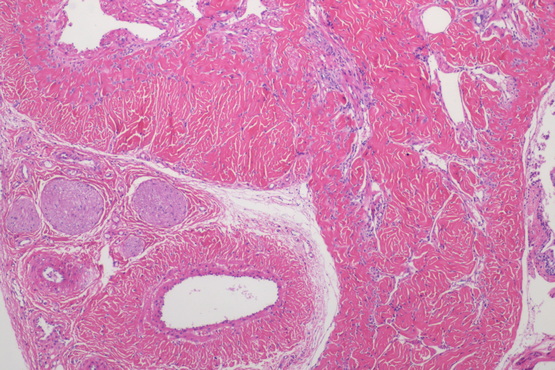

HE染色是目前国内外病理诊断上广泛采用的常规染色方法。HE染色即苏木精-伊红染色法( hematoxylin-eosin staining ),是石蜡切片技术里常用的染色法之一。苏木精染液为碱性,主要使细胞核内的染色质与胞质内的核糖体着紫蓝色;伊红为酸性染料,主要使细胞质和细胞外基质中的成分着红色。一张做工精良的HE切片是病理医生得以做出正确诊断的关键。而一台性能优良的显微镜和成像清晰的摄像头则是病理医生做出正确诊断的最重要的工具。生物显微镜ML31用于HE染色观察,具有易用舒适,稳定可靠的优势。

近期,明美广州区域安装生物显微镜ML31搭配630万像素显微镜相机MS60,用于HE染色片的观察并能清晰拍照。在显微镜下做诊断其实并不容易,这需要大量知识的学习和丰富的经验积累,而好的显微镜能有效提升效率,ML31采用高平场性物镜,保证10X/22视野数下的平坦清晰成像。